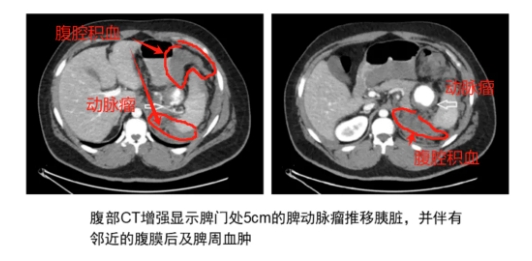

(2)脾动脉瘤破裂时影像学表现